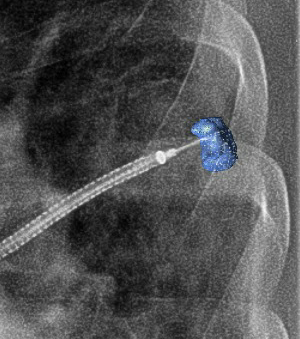

Ramsy Abdelghani, MD@Rabdelgh·

Cool case: 4.5mm partially solid PET-Avid LLL nodule. Used High PEEP/Tidal volume and wedged left side up to decrease dependent atelectasis. Navigated with Ion and adjusted with Philips CBCT. ROSE positive for Adenocarcinoma. Exciting times in lung cancer care! #ION #cbct